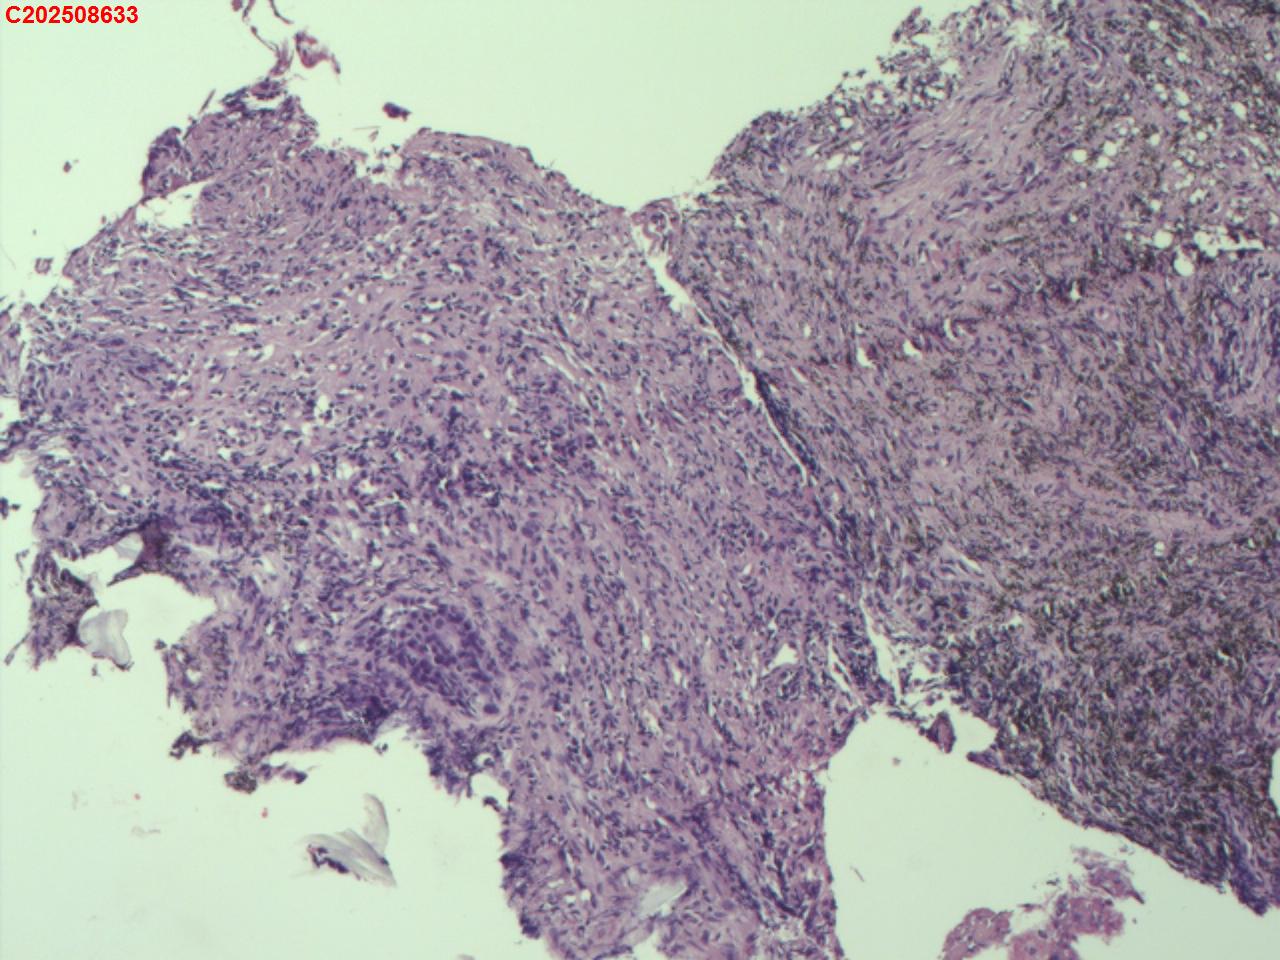

性别年龄82岁临床诊断肺结核?肿瘤?肺部感染?

大体所见2025-07-25 气管镜检查示:左侧主支气管、上叶、下叶及各段支气管未见异常。右侧主支气管未见异常。右侧中间段支气管可见碳沫沉积。右肺上叶前段支气管开口可见脓苔附着,支气管开口狭窄,内可见灰黑色新生物阻塞右肺上叶前段支气管管腔。2025-07-25结核感染T细胞检测阳性。2025-07-27肺泡灌洗液查结核分枝杆菌复合群阳性。

坏死物比较多,没有看到明确的肿瘤性病变,可以考虑给一个描述性诊断。